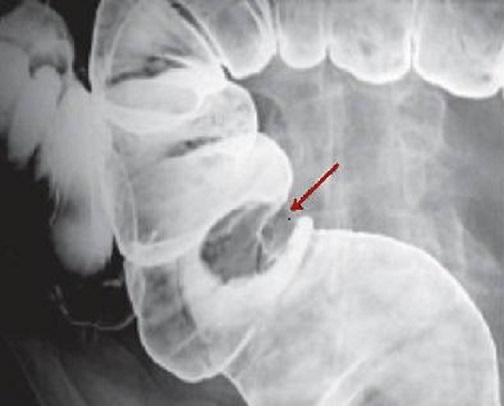

Aspect laculaire a bord

lisse pedicule d'une polyp du colon ascendant (

fleche rouge ) . Image radiologique de lavement

baryte a mono- contrast du colon . |